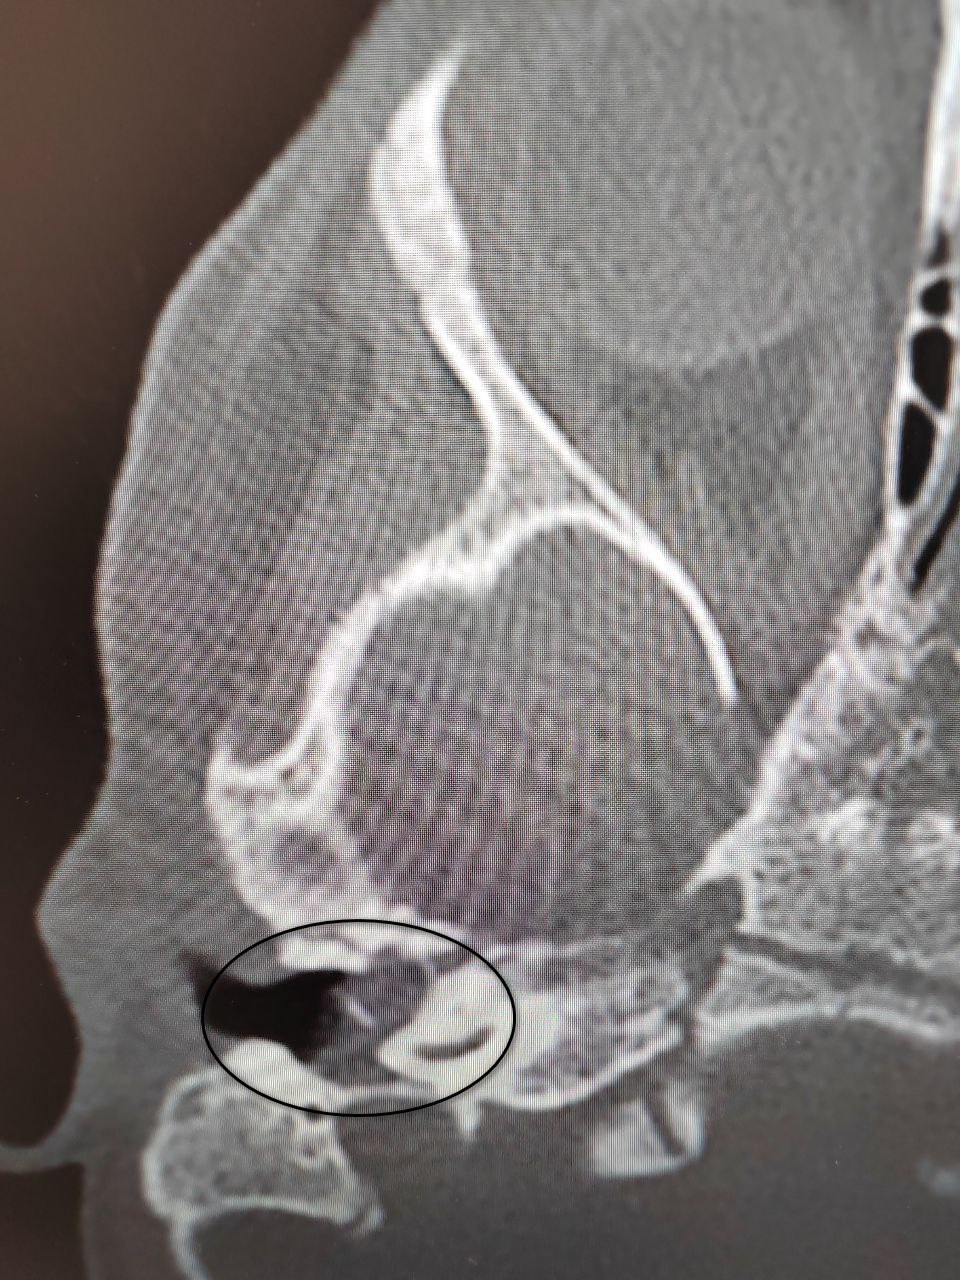

Специалисты оториноларингологического отделения Воронежской областной детской клинической больницы №1 успешно прооперировали двухлетнюю пациентку с диагностированной врожденной холестеатомой барабанной полости. Данное кистозное образование в среднем ухе редко выявляют в столь раннем возрасте – обычно заболевание обнаруживают у детей 5-8 лет.

Поводом для обращения стало ухудшение состояния после перенесенной ОРВИ: у ребенка появились боли в ухе, а консервативная терапия не принесла результатов. Ситуация осложнилась развитием пареза лицевого нерва, проявлявшегося слабостью мимических мышц. После подтверждения диагноза врачи приняли решение о проведении срочного хирургического вмешательства.

Операцию выполнил заведующий отделением Антон Мащенко, проведя аттико-антротомию с тимпанопластикой. С использованием операционного микроскопа хирург удалил холестеатому, выполнил декомпрессию лицевого нерва и восстановил механизм звукопроведения. Благодаря своевременному вмешательству медикам удалось полностью сохранить слух ребенка и восстановить функцию нерва. Девочка была выписана домой на пятые сутки после операции без каких-либо осложнений.